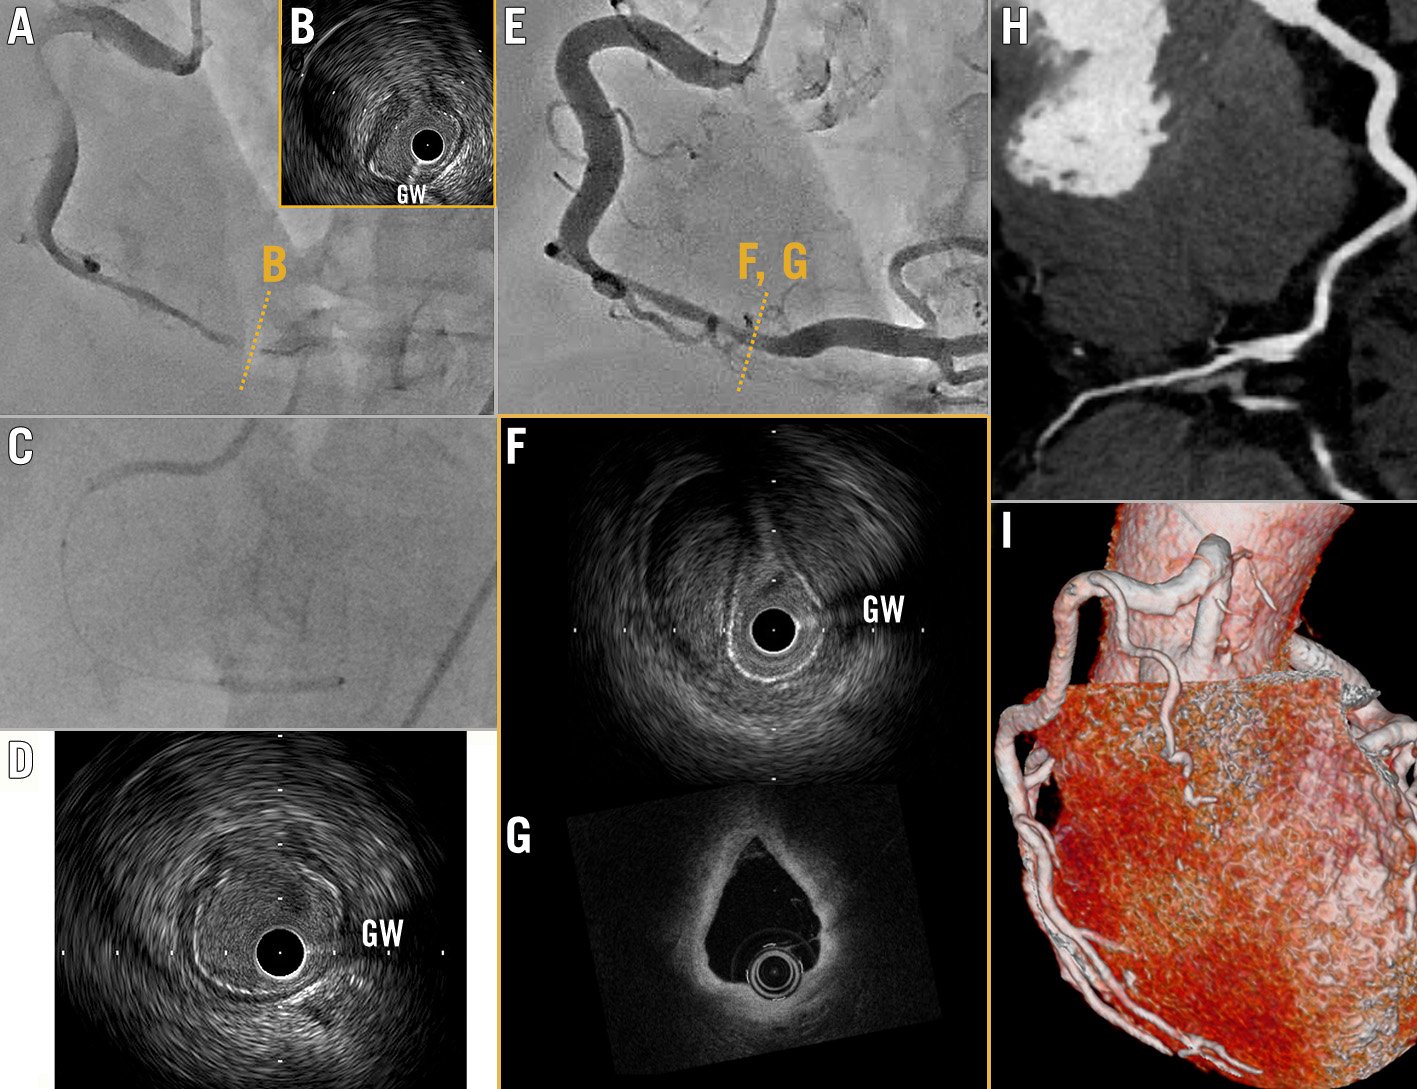

A 70-year-old woman with no history of cardiovascular disease was admitted to our hospital for inferior ST-segment elevation myocardial infarction. Urgent coronary angiography (CAG) revealed severe stenosis with Thrombolysis and Myocardial Infarction (TIMI) flow grade 1 in the right coronary artery (RCA) (Figure 1A, Moving image 1). Due to anterograde flow impairment and ongoing ischaemia, we dilated the lesion with a 2.0 mm balloon catheter (Sapphire II; OrbusNeich). Intravascular ultrasound (IVUS) imaging (AltaView; Terumo) clearly showed an intimal flap (Figure 1B, Moving image 2) and a massive intramural haematoma (IMH) at the proximal end of the flap. We diagnosed the patient with retrograde spontaneous coronary artery dissection (SCAD). We performed a long inflation, for 5 min, with a 2.5 mm perfusion balloon (PB) (Ryusei; Kaneka Medix) (Figure 1C). Satisfactory acute gain was achieved (Figure 1D, Moving image 3) and TIMI flow grade 3 was obtained without IMH propagation. On the 14th day of hospitalisation, CAG revealed moderate stenosis in the RCA (Figure 1E), even though the level of fractional flow reserve (FFR) was 0.95. Optical coherence tomography (OCT) and IVUS clearly showed the healed flap without IMH propagation (Figure 1F, Figure 1G, Moving image 4, Moving image 5). Therefore, we decided to defer from performing additional percutaneous coronary interventions. Three months later, the patient’s coronary computed tomography showed the lesion to be completely healed (Figure 1H, Figure 1I). Since a PB has the advantage of maintaining blood flow during balloon inflation, repeated dilatation of the target lesion for longer than several minutes was possible. Although PB have been used as bailout devices in cases of vessel perforation, occlusive dissections, and thrombotic occlusions1, long inflation using PB may be useful not only to prevent acute recoil but also to seal and heal the flap in patients with SCAD, without risk of late pathology related to metallic platforms or late malapposition due to IMH disappearance over time.

Figure 1. Intimal flap sealing with perfusion balloon. A) Coronary angiography (CAG) reveals significant stenosis in the right coronary artery. B) Intravascular ultrasound (IVUS) shows massive intramural haematoma and flap. C) Long inflation with a 2.5 mm perfusion balloon. D) IVUS shows satisfactory acute gain was achieved. E) Follow-up CAG on the 14th day of hospitalisation. F) IVUS and (G) optical coherence tomography (OCT) show the healed flap. H,I) Coronary computed tomography shows completely healed lesion 3 months later. GW: guidewire artefact